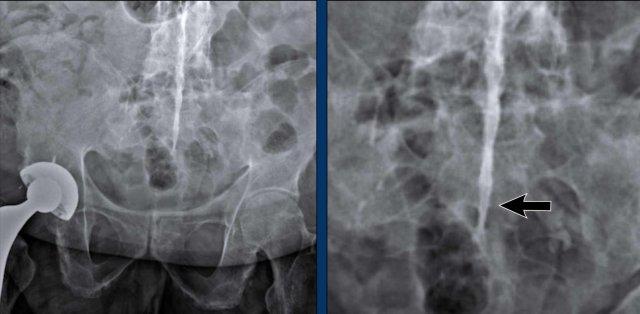

Viêm Khớp Cùng Chậu

Viêm khớp cùng chậu là một đặc điểm quan trọng của SpA.

Bệnh khởi đầu bằng viêm, biểu hiện trên MRI dưới dạng phù nề, có hoặc không kèm theo bào mòn (quan sát được trên MRI và hình ảnh học thông thường).

Về sau sẽ thấy chuyển sản mỡ trên MRI hoặc xơ cứng dọc theo khớp cùng chậu trên X-quang.

Giai đoạn cuối là dính khớp cùng chậu.

X-quang

Xơ cứng dưới sụn và bào mòn hai bên khớp cùng chậu do viêm khớp cùng chậu.

MRI

MRI chuỗi xung T1W sau tiêm thuốc tương phản từ của cùng bệnh nhân cho thấy bờ khớp cùng chậu không đều do bào mòn.

Có ngấm thuốc ở xương dưới sụn và phù nề tủy xương.

Không có tràn dịch khớp.

Cuộn qua các hình ảnh MRI và so sánh với các dấu hiệu trên X-quang (hình ảnh cuối cùng).

Chẩn đoán phân biệt viêm khớp cùng chậu:

- Thoái hóa khớp: xơ cứng dưới sụn hai bên khớp cùng chậu không kèm bào mòn.

- Viêm xương đặc xương chậu (Osteitis condensans ilii): xơ cứng hình tam giác hai bên ở xương chậu tiếp giáp với khớp cùng chậu.

Chẩn đoán viêm khớp cùng chậu có thể gặp khó khăn khi chỉ dựa vào X-quang. Việc bổ sung X-quang cột sống thắt lưng hoặc các phương tiện chẩn đoán khác có thể giúp tăng độ chắc chắn trong chẩn đoán.

Viêm khớp cùng chậu giai đoạn muộn với dính khớp cùng chậu.